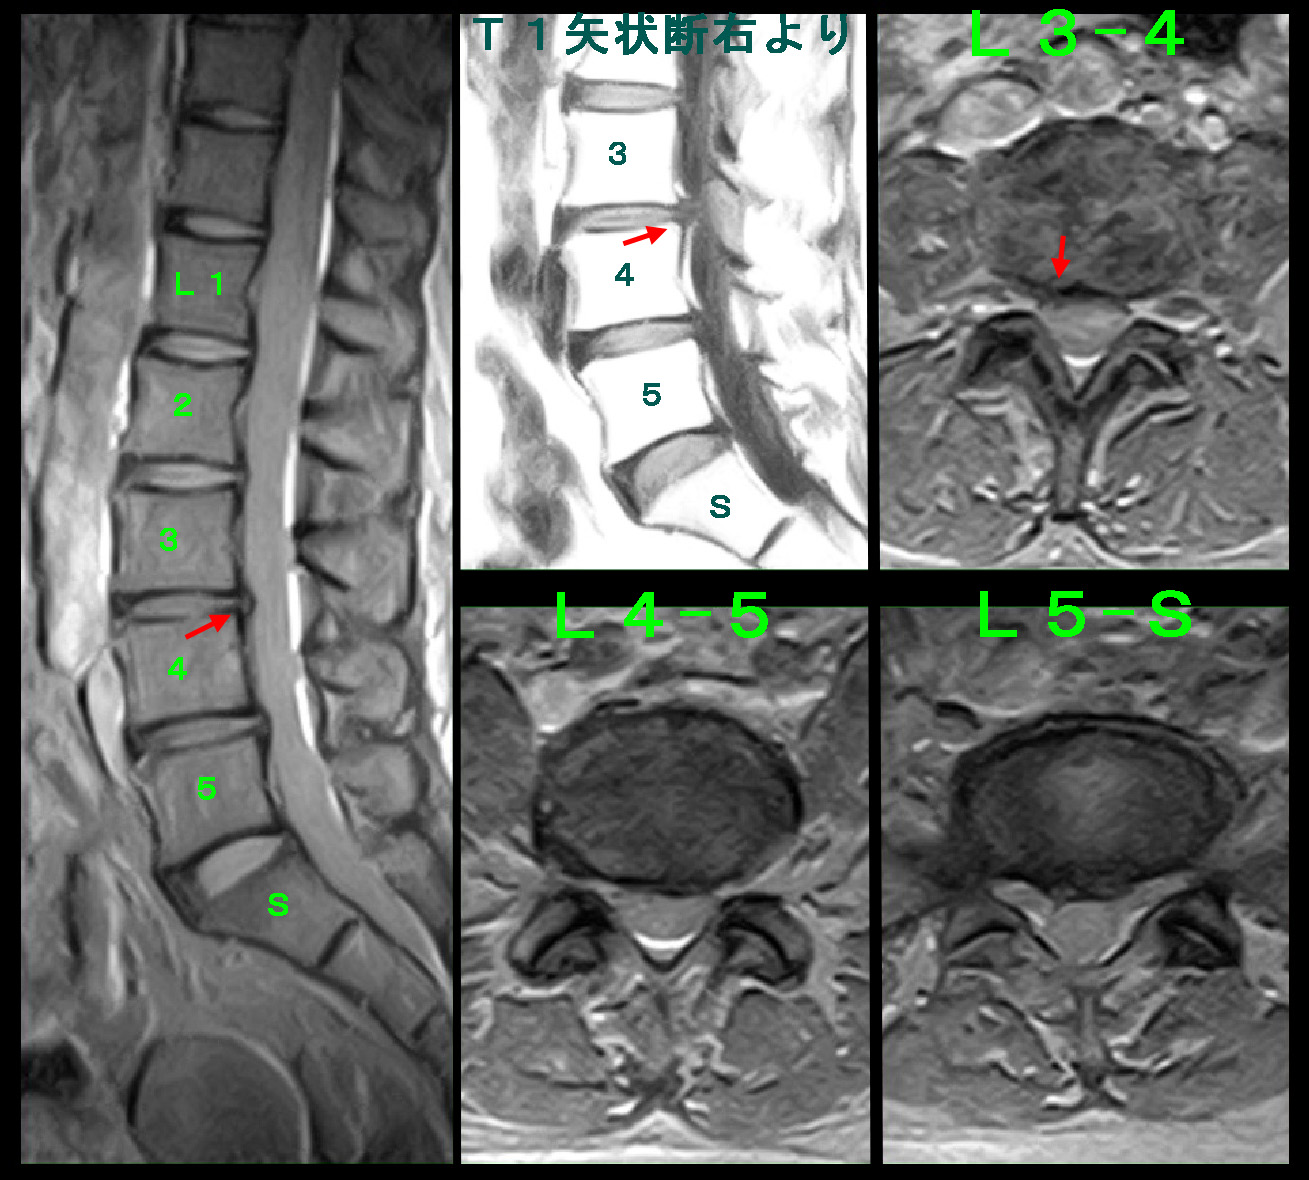

次の患者さんは83才の女性です。平成27年10月30日車いすで受診されました。同年5月14日から9月21日まで整形外科病院に腰痛と両下肢の鈍痛(坐骨神経痛です)で歩行困難となり入院していたけれど、症状は軽減せず歩行可能とはならなかったとのことでした。腰椎MRI検査ではL3-4高位で重度の脊髄圧迫(脊柱管狭窄と表現します)を認めました。これが腰痛と両下肢の鈍痛の病因です。

当院ではこのように長期坐骨神経痛が継続している患者さんには、週に1回連続3回の神経根ブロックを行ってみることを勧めています。この方にも両側L4神経根ブロックをそのように行いましたが、歩行が可能となることはありませんでしたが、VAS8(とても痛い)は2(わずかに痛い)に軽減したとのことでした。